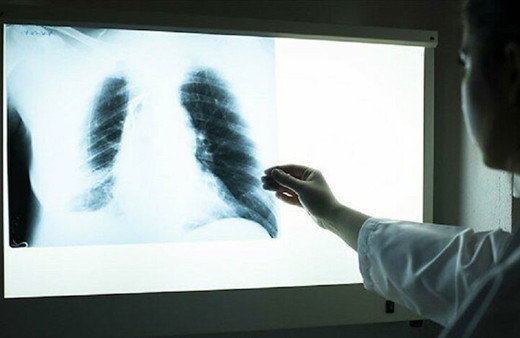

Akciğer